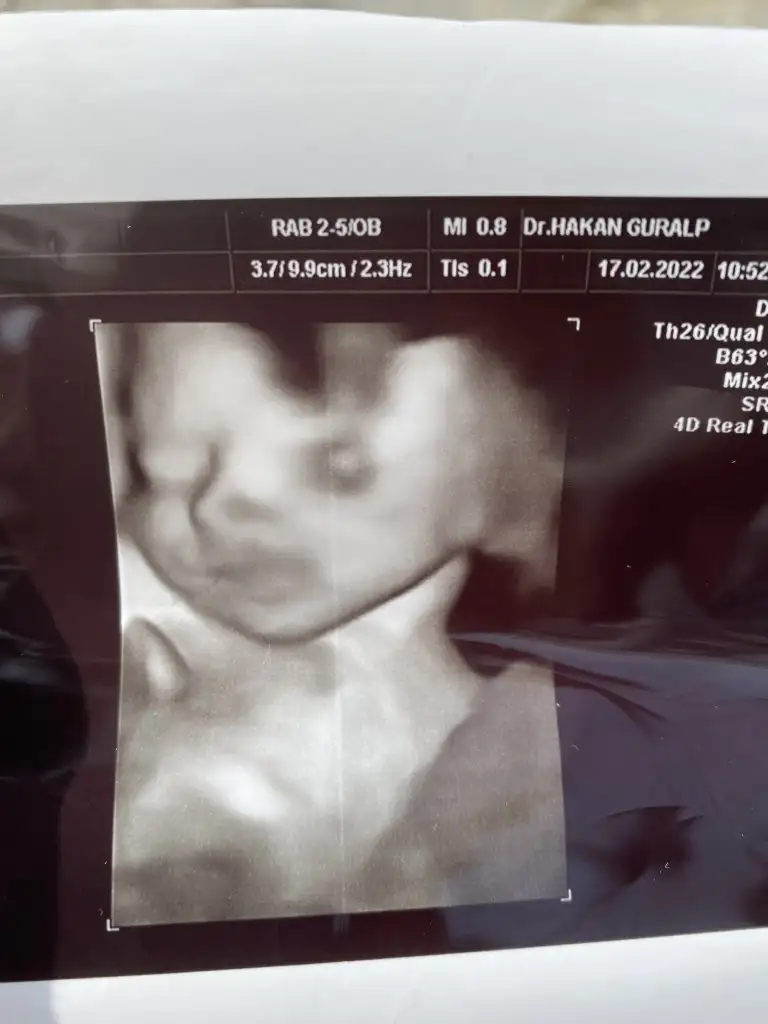

Oh çok şükür:) bu haftalarda böyle durumlar çok olabiliyor bence. Sen kendini hiç yorma tuvalet dışında kalkma. Geçen her gün önemli sonuçta. Ama çok şükür bebek iyi maşallahKızlar 1 hafta istirahat verdi doktor annem gelip bakacak bana. Adalat Protestan verdi. Nstde sancı çıkmadı. Kalp atışı iyi. Allah’a şükür açılmam yok bebiş iyi bir de yüzünü gösterdi ilk kez hiç uğraştırmadan. 1100 gram olmuş.

Oyss kuzum benim yesinler onun o minik yüzünüKızlar 1 hafta istirahat verdi doktor annem gelip bakacak bana. Adalat Protestan verdi. Nstde sancı çıkmadı. Kalp atışı iyi. Allah’a şükür açılmam yok bebiş iyi bir de yüzünü gösterdi ilk kez hiç uğraştırmadan. 1100 gram olmuş.